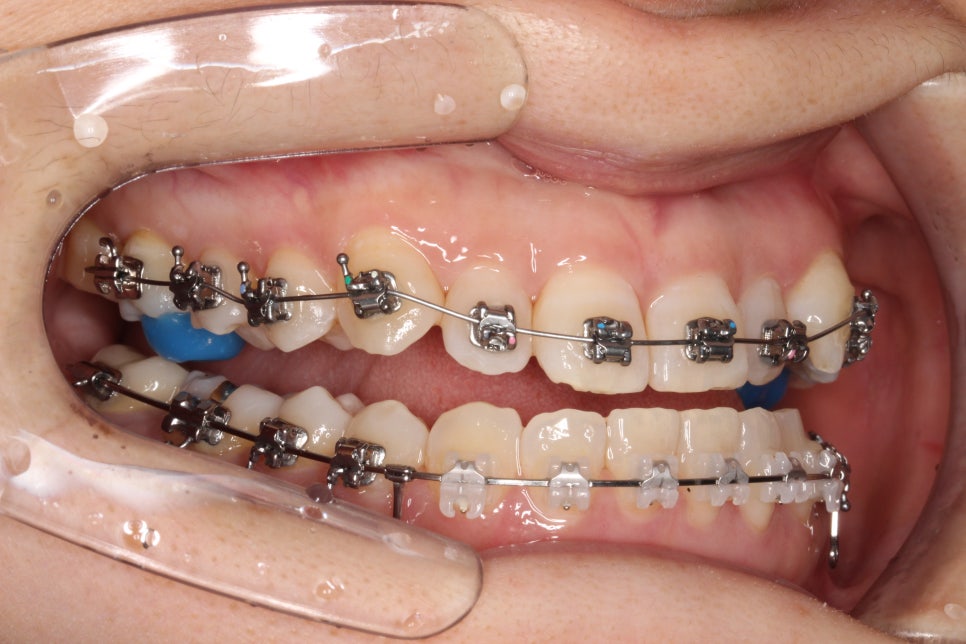

치료 초기 단계

치료를 시작한지 얼마 되지 않았을 때의 모습입니다. 아래쪽은 미니스크류를 식립하여 당기고 있고, 앞니가 넘어올 수 있게 어금니에 #바이트블록을 올렸습니다. 밥먹을 때 힘드셨을 겁니다 ㅠ